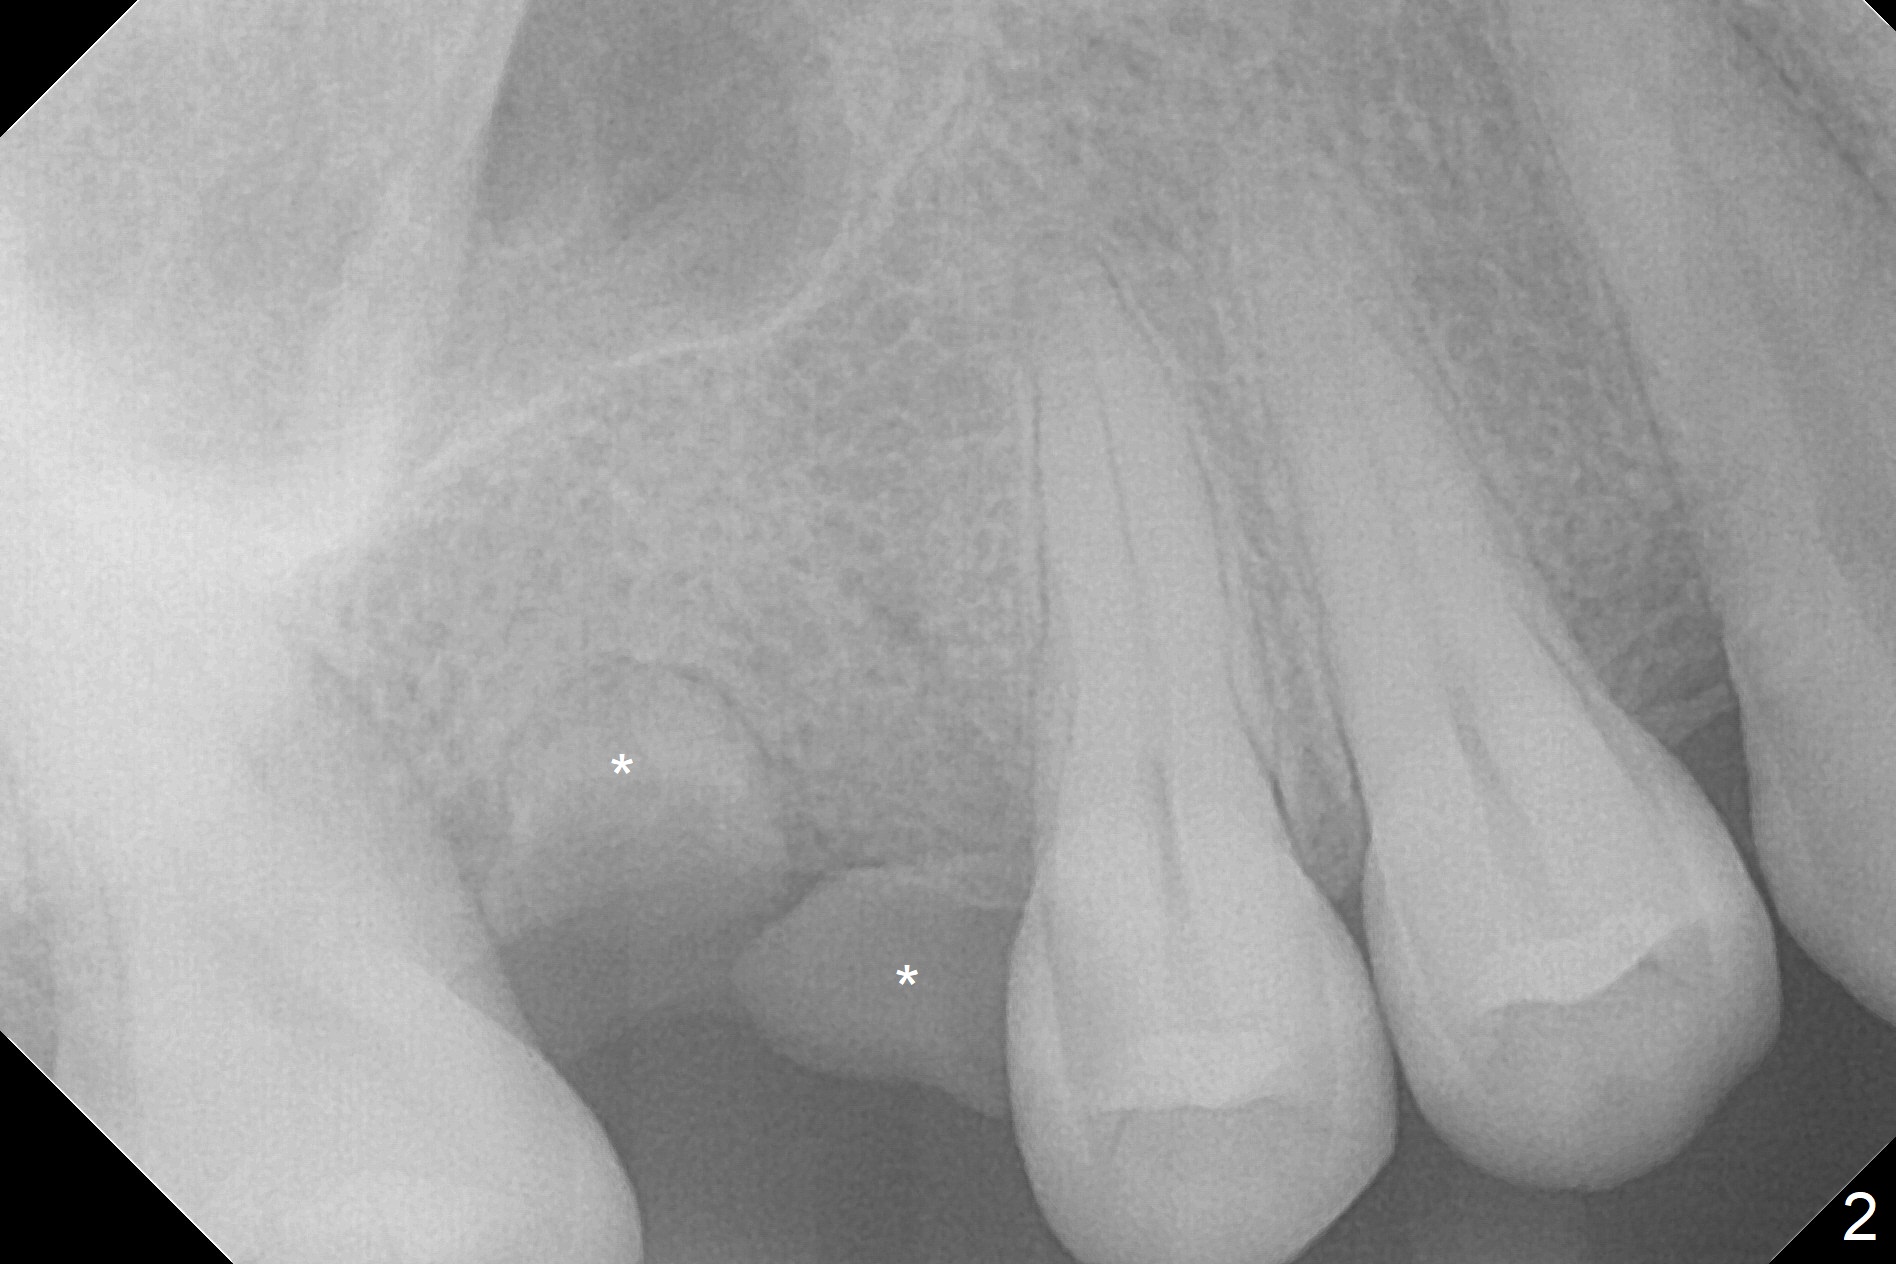

A 45-year-old woman has poor dentition due to dental phobia (Fig.1). The tooth #3 has residual roots (Fig.2 *). The initial depth will be 9 mm with starter drill, 2 mm drill (parallel pin, PA) and 3.2 mm Magic Drill (Fig.3). Use 4x11 mm dummy implant for sinus lift for the last 2 mm.